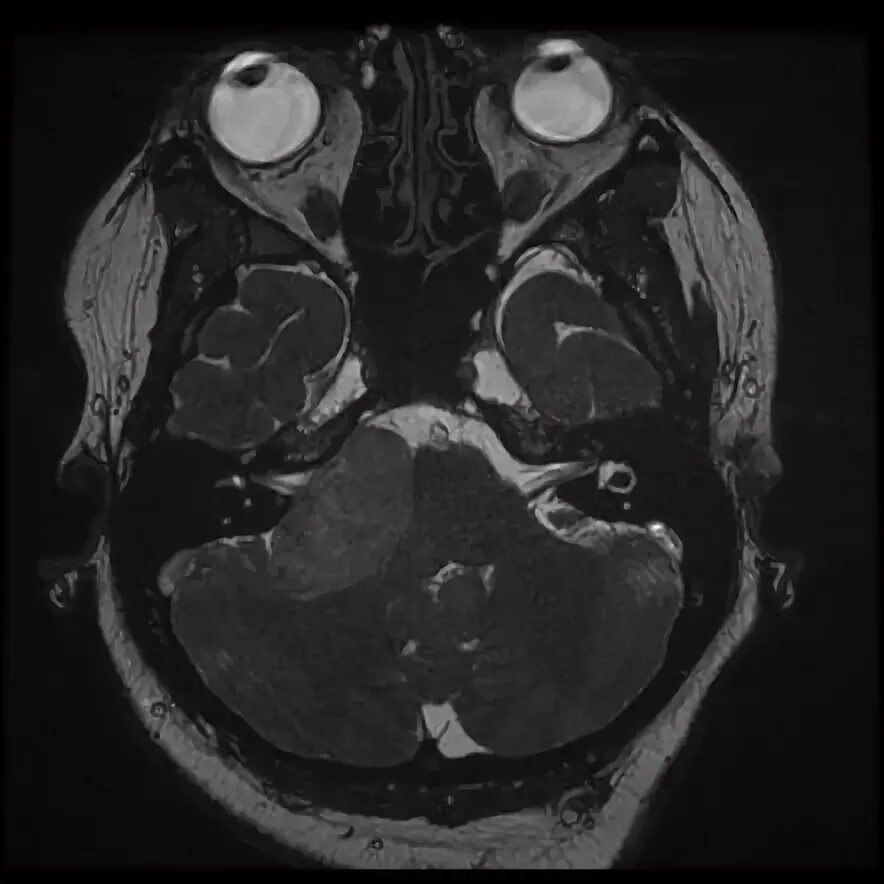

Мрт головного мозга мосто мозжечкового угла